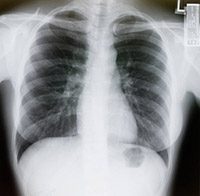

How to encourage loved ones to get spiral CT lung cancer screening

Spiral CT lung cancer screening can help save lives. Current smokers (or former smokers who quit in the past 15 years) and those who smoke about 30 packs of cigarettes a year can participate in lung cancer screening.